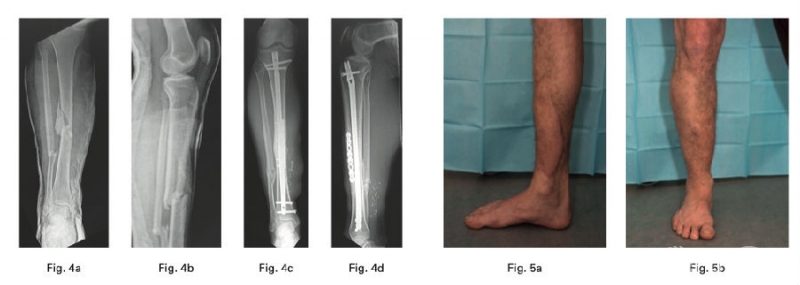

胫骨平台骨折是过去二十年研究的热点,从分型到治疗有了成熟的研究和认识。而小腿骨折和足踝部骨折因大量的手术病例和并发症,始终是研究的一个热点。

1、Hofmann A等在一项多中心随机对照研究中对比了塌陷或劈裂伴塌陷胫骨平台骨折患者骨缺损自体髂骨移植和骨水泥填充的术后效果。发现术后第一天骨水泥组患者出血和疼痛率更低,6个月随访时两组患者功能和影像学结果无明显统计学差异。

2、Hourani AI在一项病例系列中确定了使用mechanically relevant devitalized bone (ORDB)进行矫形重建是否与IIIB型开放性胫骨干骨折感染率增加相关,其结论为在IIIB型开放性胫骨干骨折治疗的情况下,在最终重建中使用ORDB是安全的。